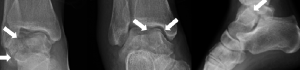

Case 1, Figure 4